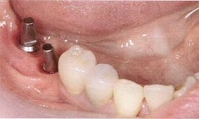

当院のインプラント症例(奥歯を失った場合)

インプラント症例(奥歯を失った場合)①術前

インプラント症例(奥歯を失った場合)①術後